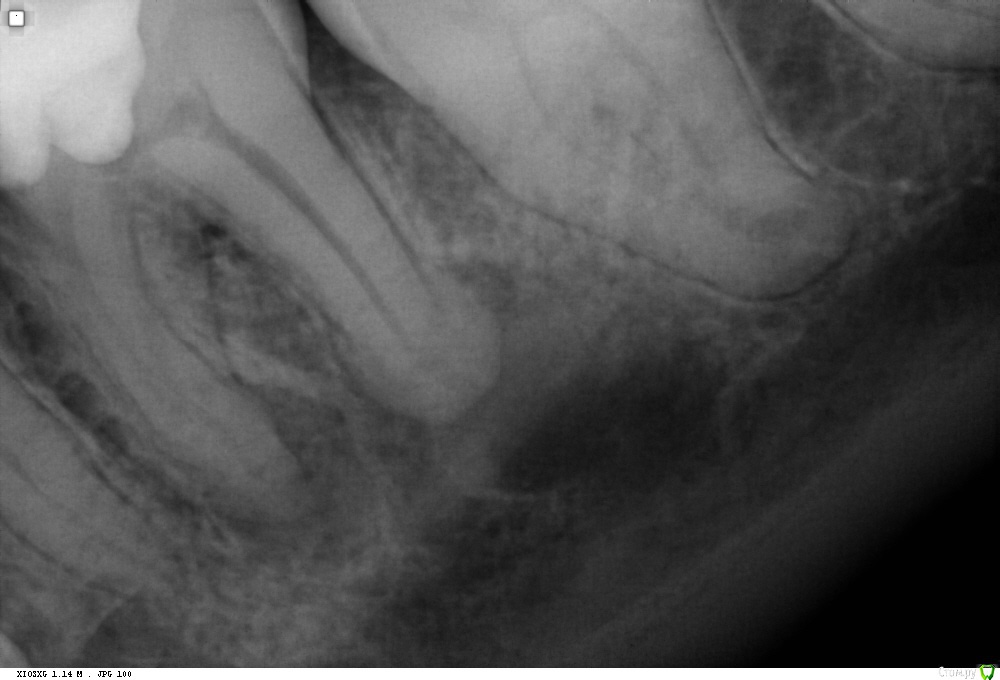

St. Опубликовано 30 января, 2018 Поделиться Опубликовано 30 января, 2018 Сейчас после повторной распломбировки, апикальный размер больше, такое впечатление что идет активная резорбция там Ссылка на комментарий